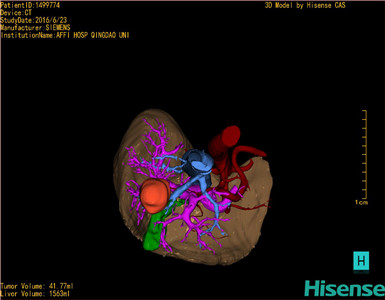

通过调节窗宽窗位调整CT序号,对肿瘤,肝实质,胆囊,下腔静脉,肿瘤,肝动脉、门静脉及肝静脉等进行三维重建;系统自动计算肿瘤体积和肝脏体积。

模拟手术操作,自动计算切除肿瘤体积。肝脏体积为1536ml,肿瘤体积为41.77ml,肿瘤体积为肝脏体积2.7%,通过比60-70岁正常肝脏体积为1262.7±284.31ml,通过术前模拟手术,精准判断切除后剩余肝脏体积能耐受,避免肝衰竭发生。

术前三维重建:

重建图片